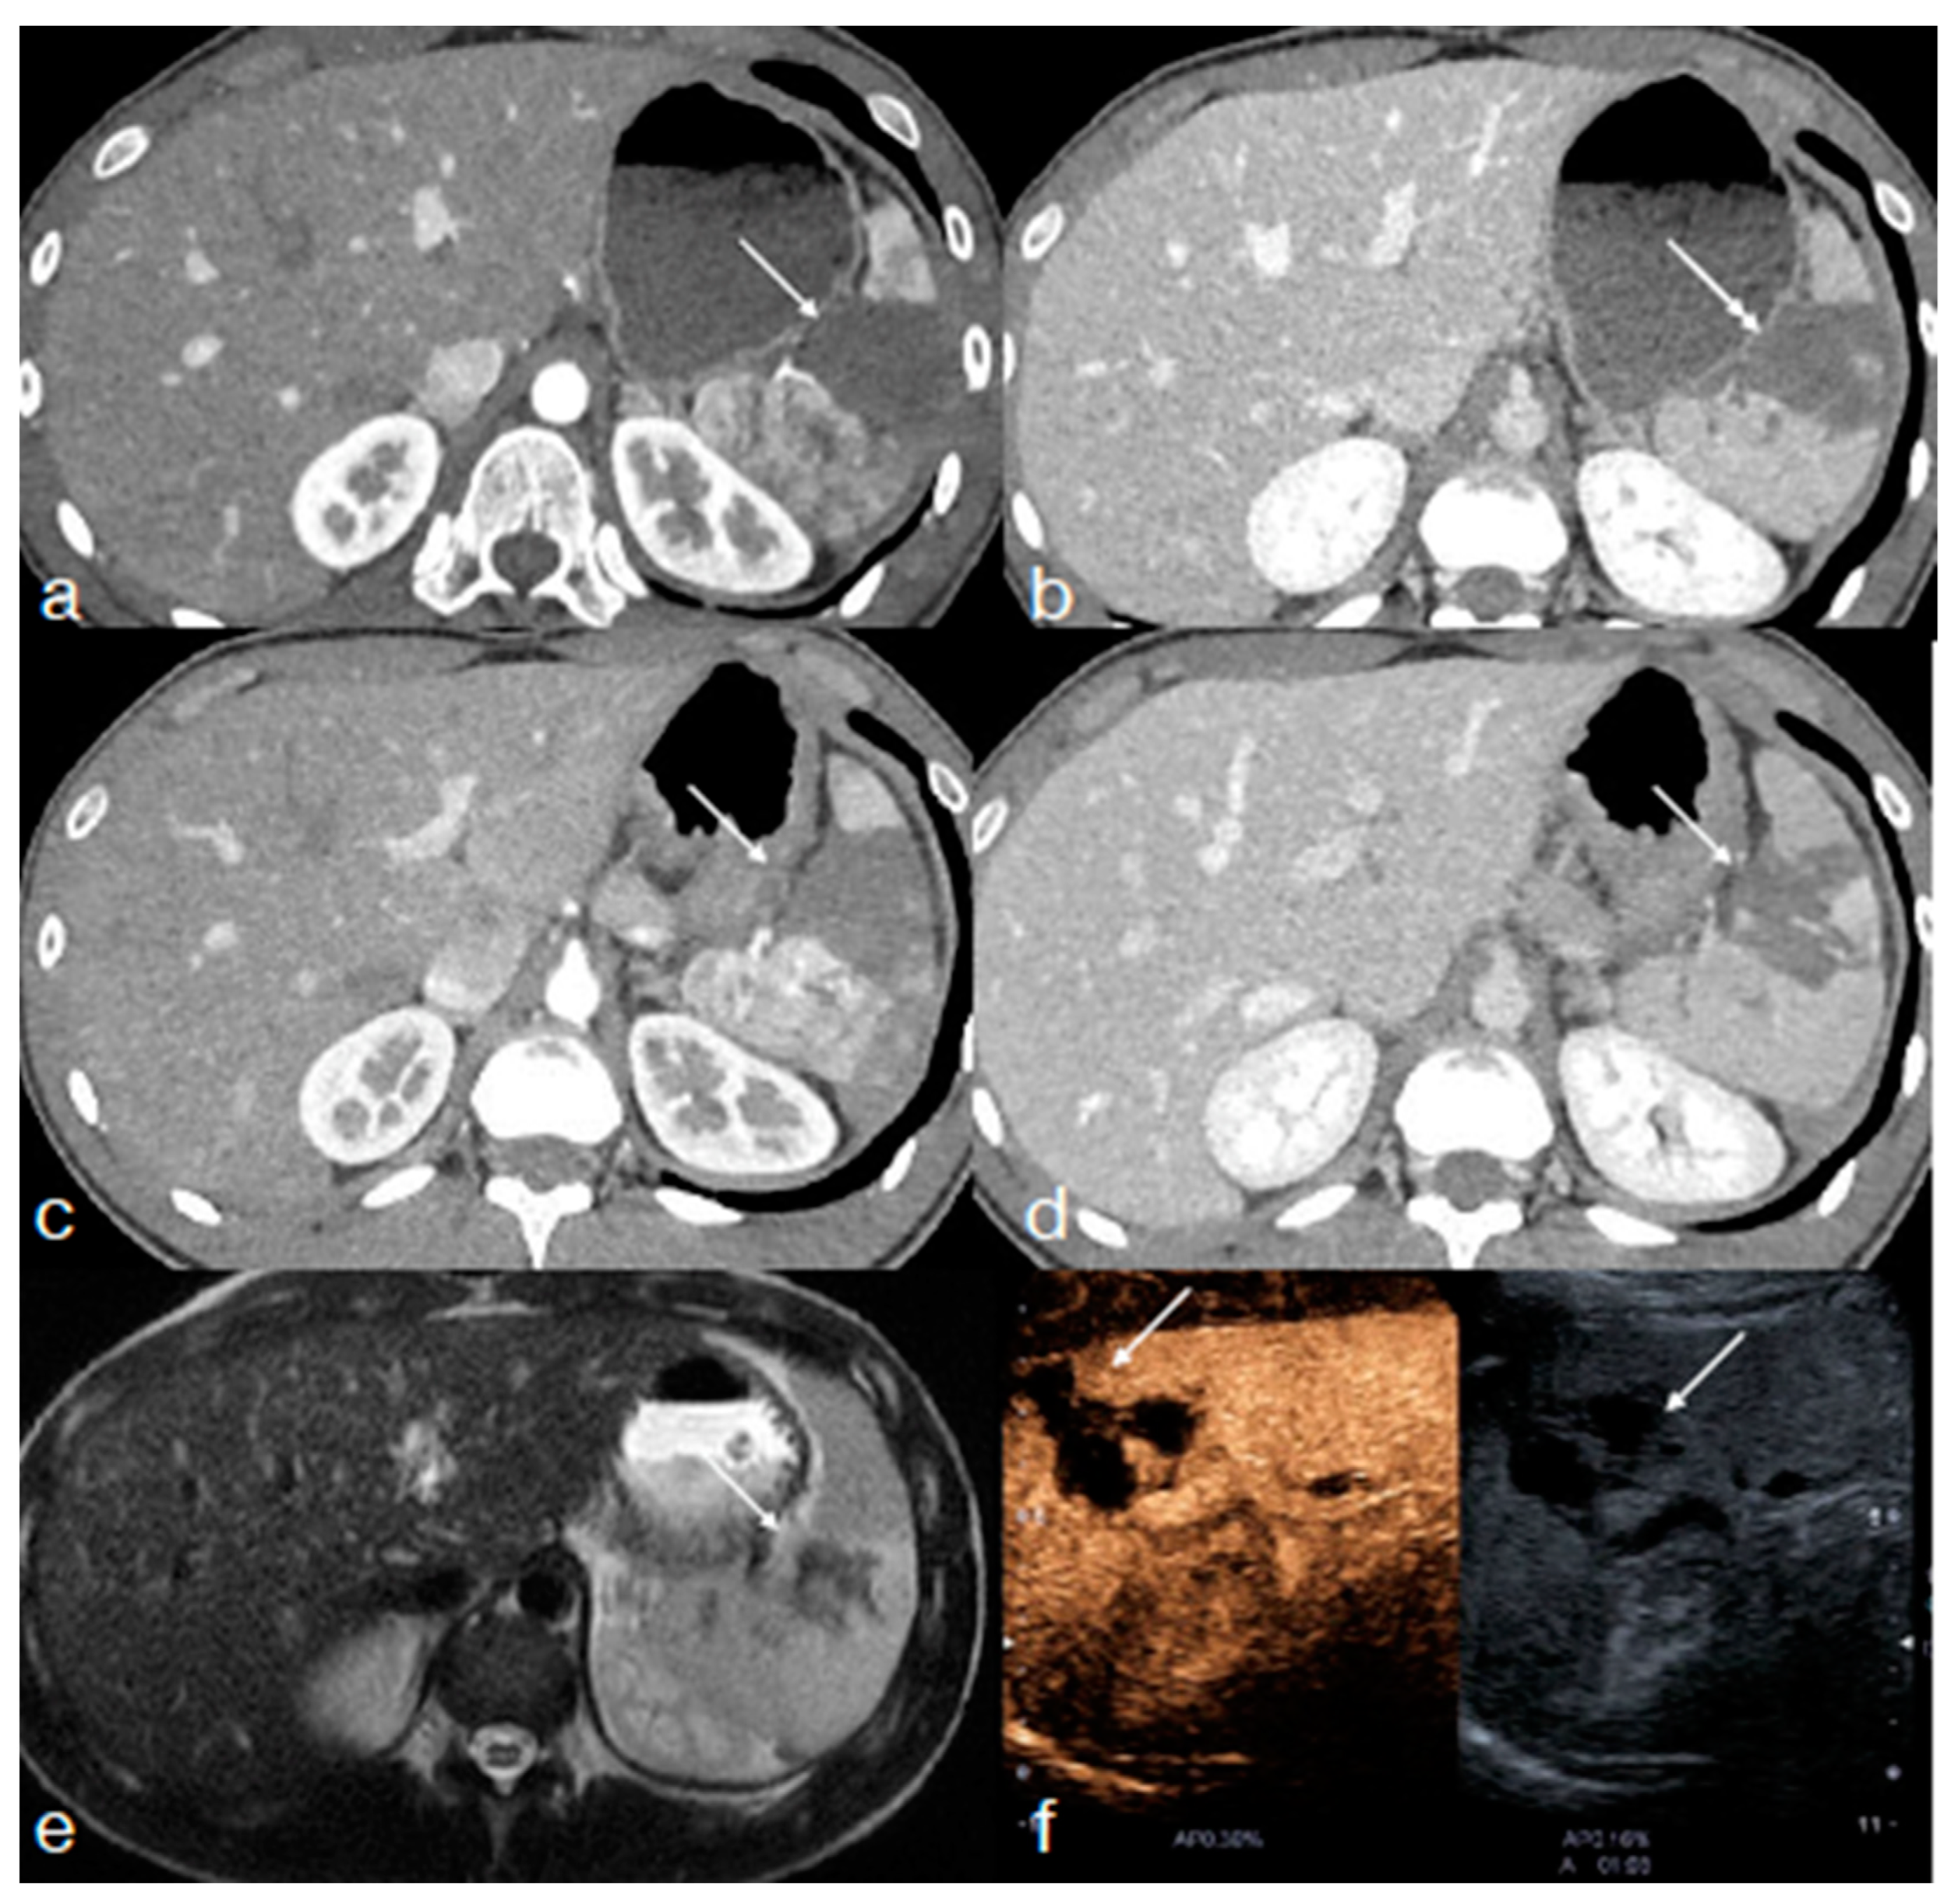

- Miele, V.; Piccolo, C.L.; Sessa, B.; Trinci, M.; Galluzzo, M. Comparison between MRI and CEUS in the follow-up of patients with blunt abdominal trauma managed conservatively. Radiol. Med. 2015, 121, 27–37. [Google Scholar] [CrossRef] [PubMed]

- Di Serafino, M.; Iacobellis, F.; Schillirò, M.L.; Ronza, R.; Verde, F.; Grimaldi, D.; Dell’Aversano Orabona, G.; Caruso, M.; Sabatino, V.; Rinaldo, C.; et al. The Technique and Advantages of Contrast-Enhanced Ultrasound in the Diagnosis and Follow-Up of Traumatic Abdomen Solid Organ Injuries. Diagnostics 2022, 12, 435. [Google Scholar] [CrossRef] [PubMed]

- Iacobellis, F.; Di Serafino, M.; Brillantino, A.; Mottola, A.; Del Giudice, S.; Stavolo, C.; Festa, P.; Patlas, M.N.; Scaglione, M.; Romano, L. Role of MRI in early follow-up of patients with solid organ injuries: How and why we do it? Radiol. Med. 2021, 126, 1328–1334. [Google Scholar] [CrossRef] [PubMed]